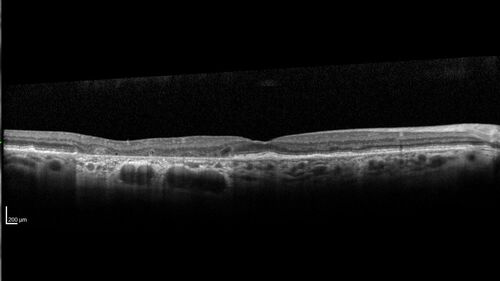

Geographic Atrophy with recent vision loss left eye

80 year old Recent vision loss in the left eye for about 6 weeks.

VA 20/25 OD, 20/63 OS (was 20/40 5/3/21 at patients first visit)